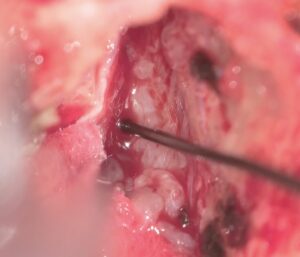

外視鏡を用いると吻合時にはデジタルズームをフットスイッチで入れると瞬時に高拡大にできます。

糸が通ったら、また瞬時にデジタルズームを切ります。

そして糸を結びます

次の針はまち針のように通してあり、しかも糸は常に繋がっていますので、針は無くなりません(Needle parking mehtod)